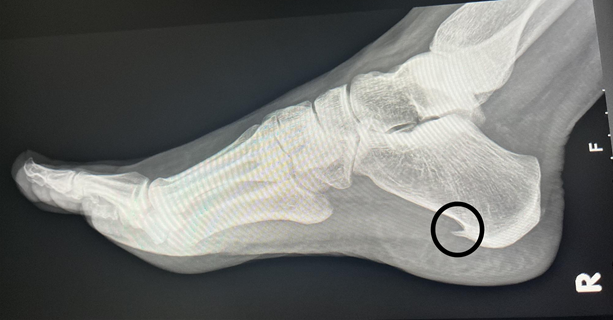

U današnjem članku vam pišemo na temu petnog trna  jedne od najupornijih i najiritantnijih tegoba stopala koja, iako nije opasna po život, može svakodnevnicu pretvoriti u pravi izazov.